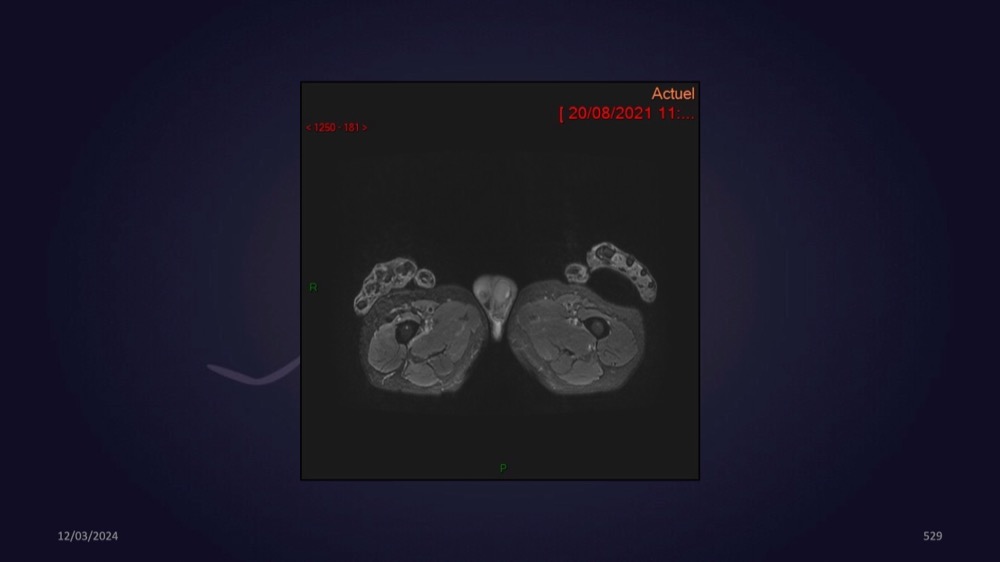

Mezhgani / Dimitri Boulos / Carlier 23/03/2022